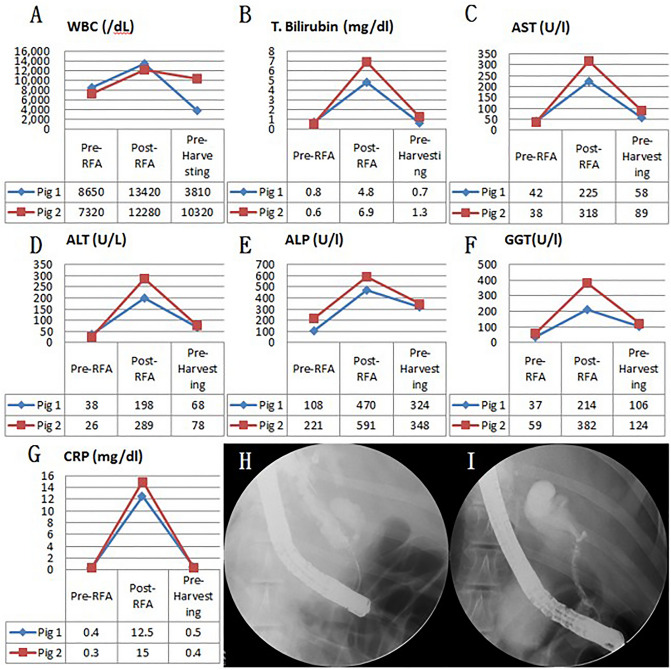

Fluoroscopic analysis via ERCP and blood analysis

In all six swine animal models, we succeeded in generating BSS using intraductal RFA without any complications such as bleeding or perforation (success rate = 100% (6/6), severe complication rate = 0%). Blood levels of WBC, AST, ALT, ALP, GGT, and CRP of all experimental animals were measured before the intraductal RFA procedure, after the intraductal RFA procedure (2 weeks after RFA), and before euthanizing animals (Figs. 1, 2, 3A–G). Blood levels of WBC, AST, ALT, ALP, GGT, and CRP were elevated after the intraductal RFA procedure but decreased after biliary stenting. Figure 1H,I are biliary fluoroscopy findings at 2 weeks after RFA in experimental animals 1 and 2, demonstrating biliary stenosis. The same trend of blood test results as in Fig. 1 was observed in Fig. 2. The difference between Figs. 1 and 2 was that the follow-up was performed at 3 months after biliary stenting in Fig. 2. Biliary stenosis was confirmed by fluoroscopy findings at 2 weeks after RFA in experimental animals 3 and 4 (Fig. 2H,I). Experimental animals 5 and 6 were followed for 5 months after biliary stenting. They showed the same tendency of blood test results (Fig. 3A–G). Biliary stenosis was also confirmed by fluoroscopy findings at 2 weeks after RFA in experimental animals 5 and 6 (Fig. 3H,I).